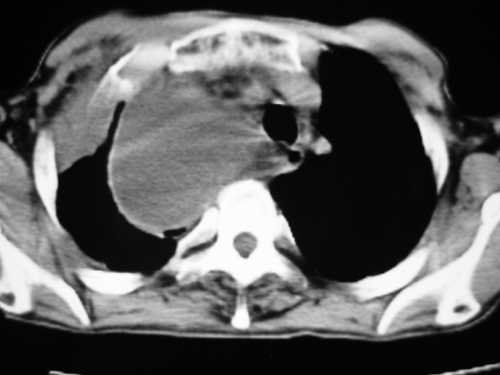

以下是引用yangyudong333在2008-4-29 5:46:00的发言:[br]1左上叶结节呈分叶状,边缘毛刺,考虑肺癌并纵隔淋巴结转移可能性大,结核待排,[br] [br]2右侧多发包裹性胸腔积液